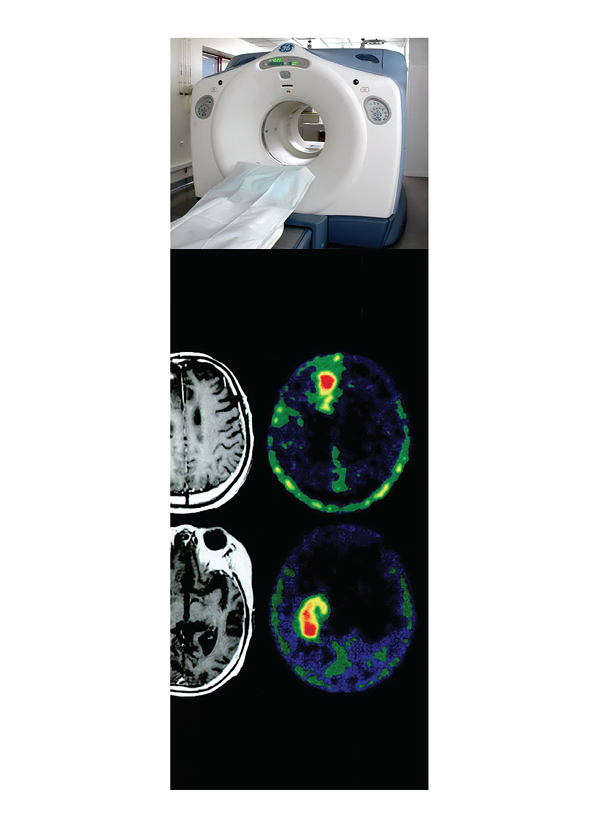

การศึกษาความเป็นไปได้และความเหมาะสมของการใช้เทคโนโลยีเพทซีทีในประเทศไทย